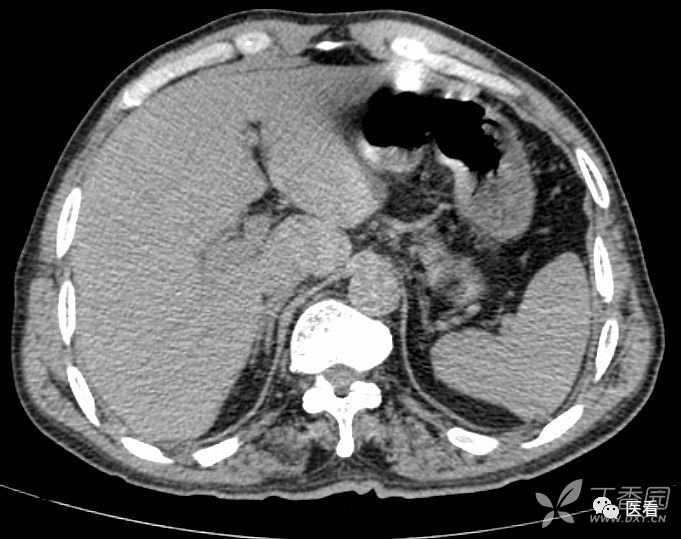

7 受检者体内、体表高密度组织结构形成的伪影

鸡冠 (红箭)所致放 射伪影 (黄箭)